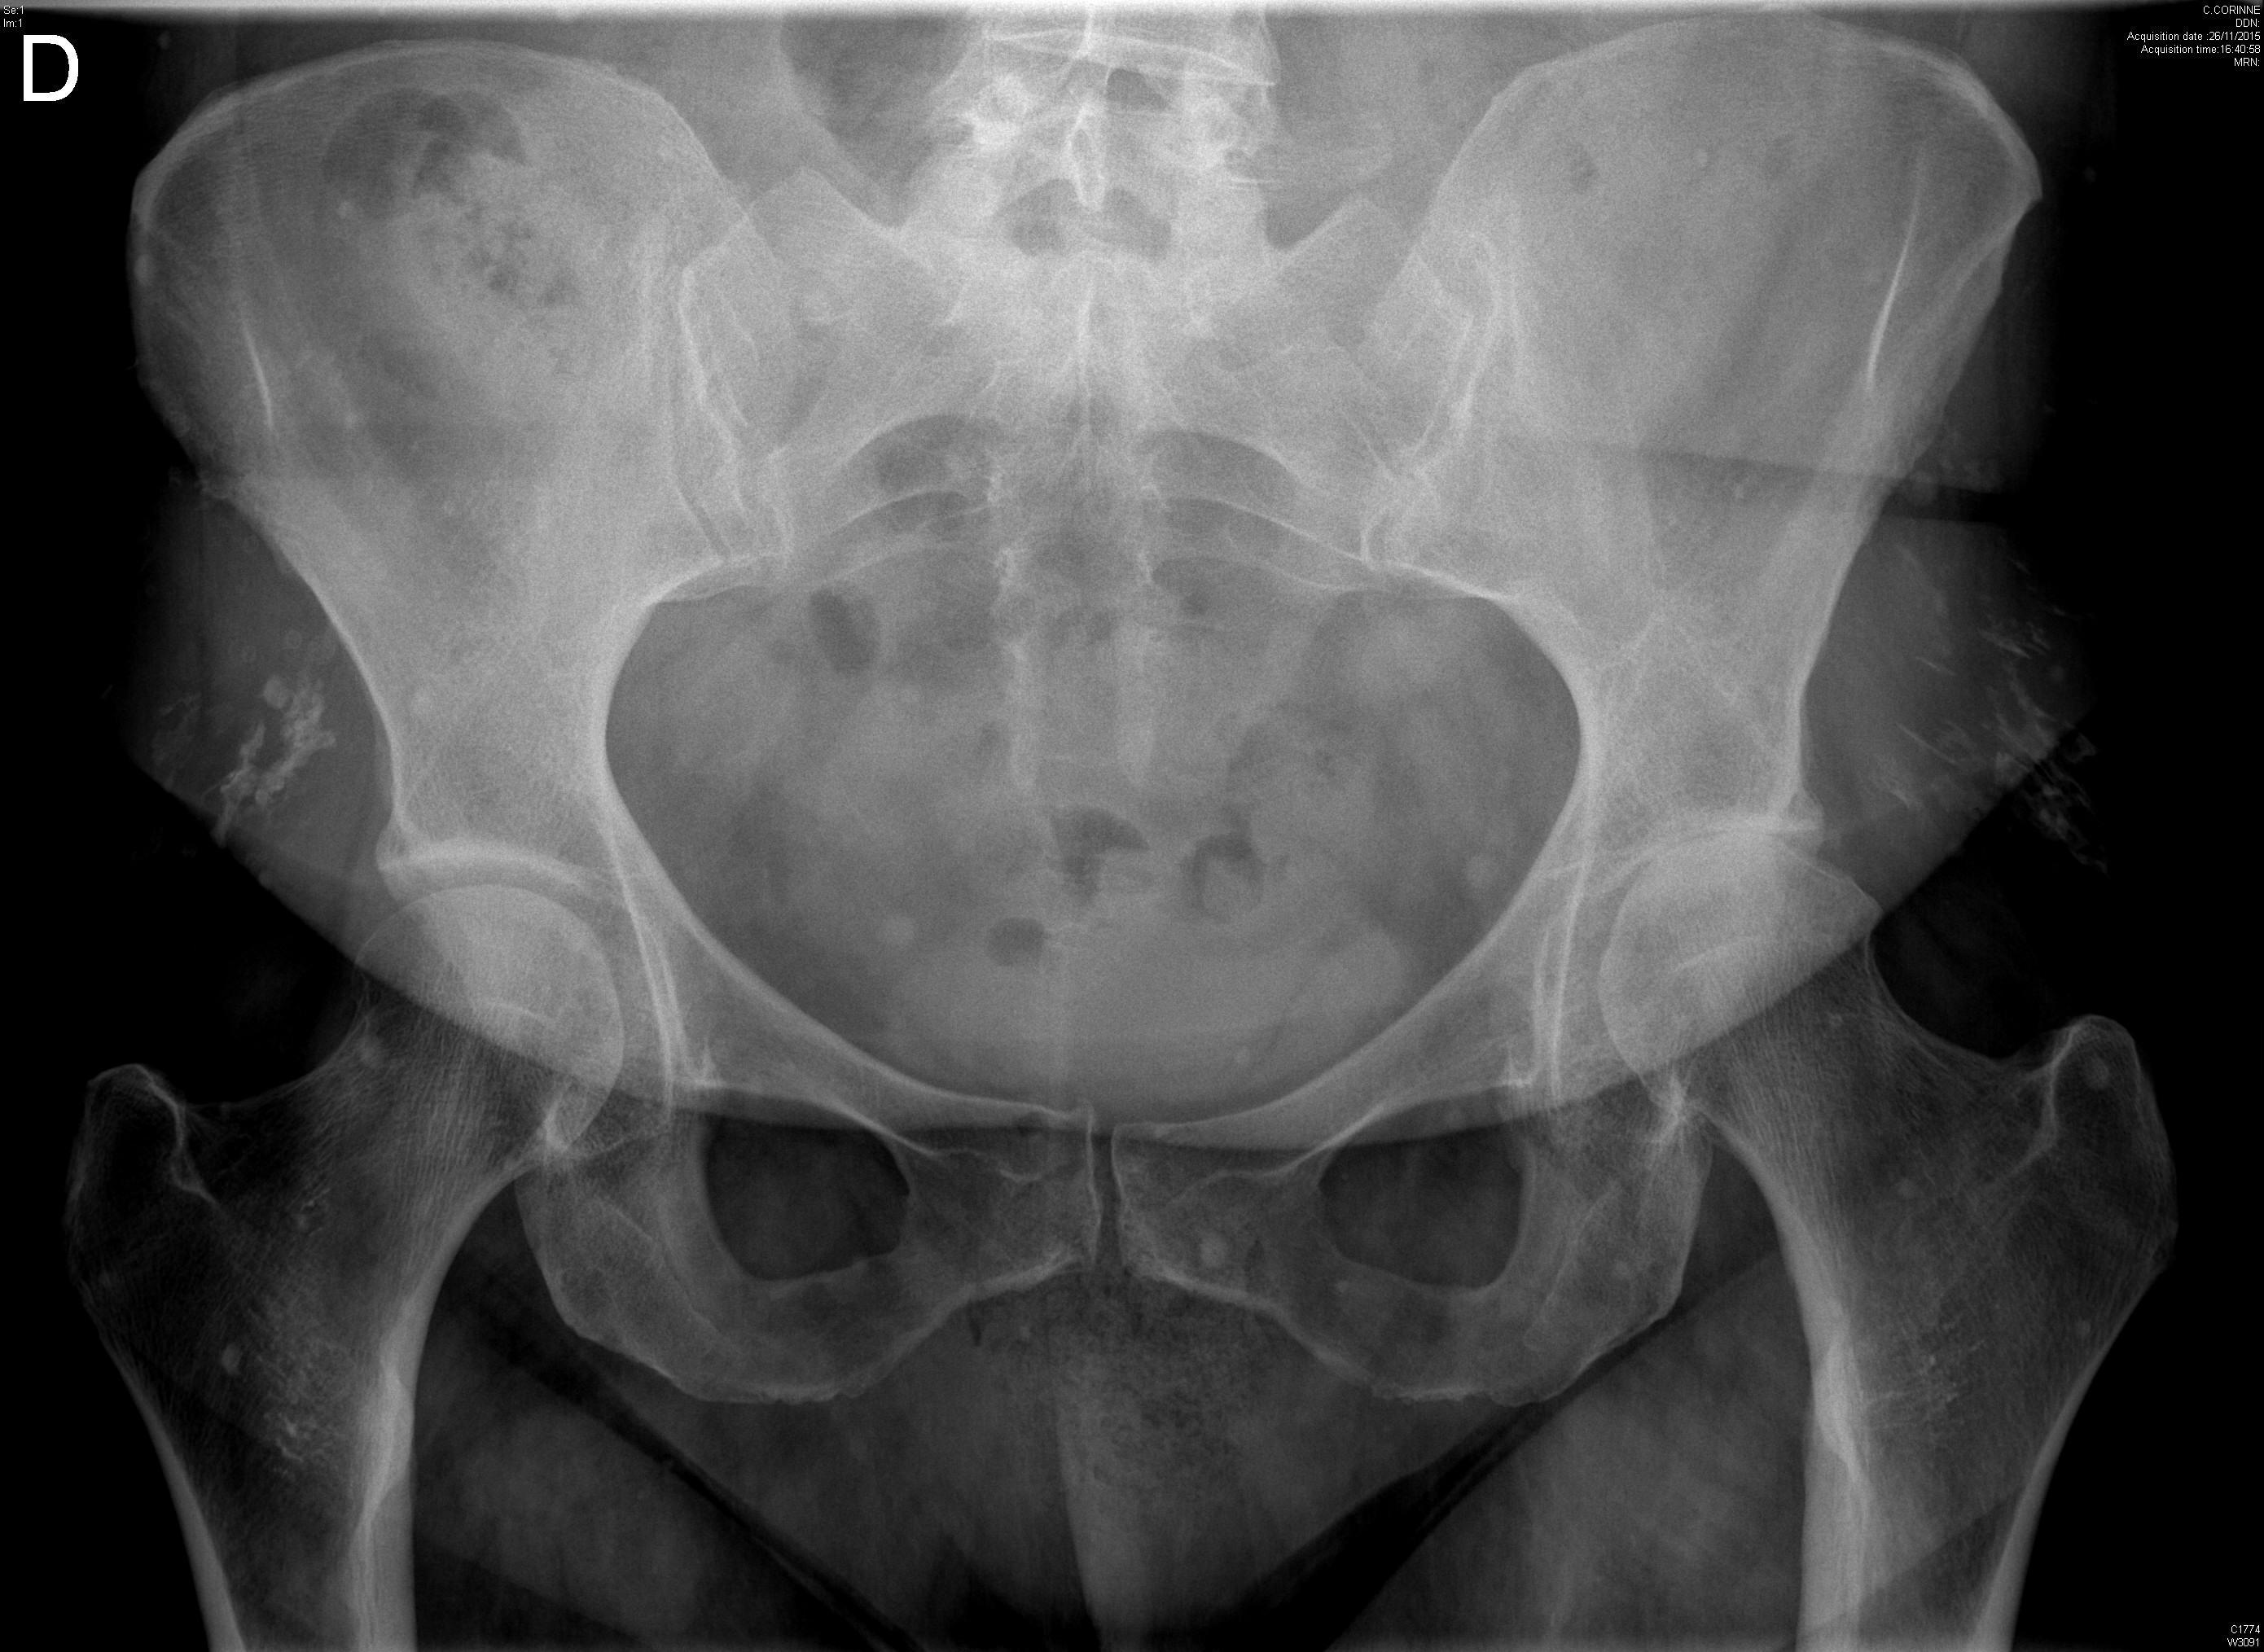

Coxite rapidement destructrice avec ostéonecrose chez une patiente traitée dans le cadre d'un syndrome des anti-synthétases

Radiographie retrouvant une dysplasie acétabulaire bilatérale ainsi qu'une lésion de dysplasie fibreuse du col fémoral droit chez une jeune fille